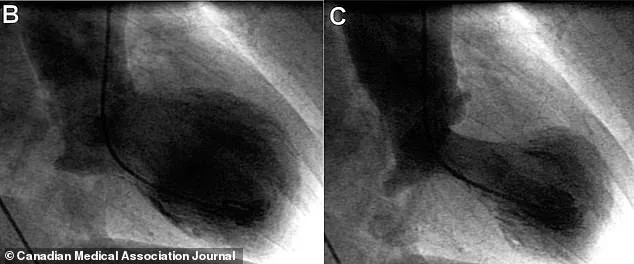

Diagnosing takotsubo syndrome is a meticulous process. Doctors first rule out a heart attack using tests like echocardiograms, which reveal a distinctive shape to the heart's left ventricle. In takotsubo syndrome, the lower part of the heart balloons outward while the neck remains narrow, resembling a Japanese octopus trap called a takotsubo. Blood tests for troponin, a protein released during heart damage, are also used. However, the definitive diagnosis requires a cardiac catheterization to confirm that no arteries are blocked. This distinction is critical: while the symptoms mirror a heart attack, the underlying causes are entirely different.